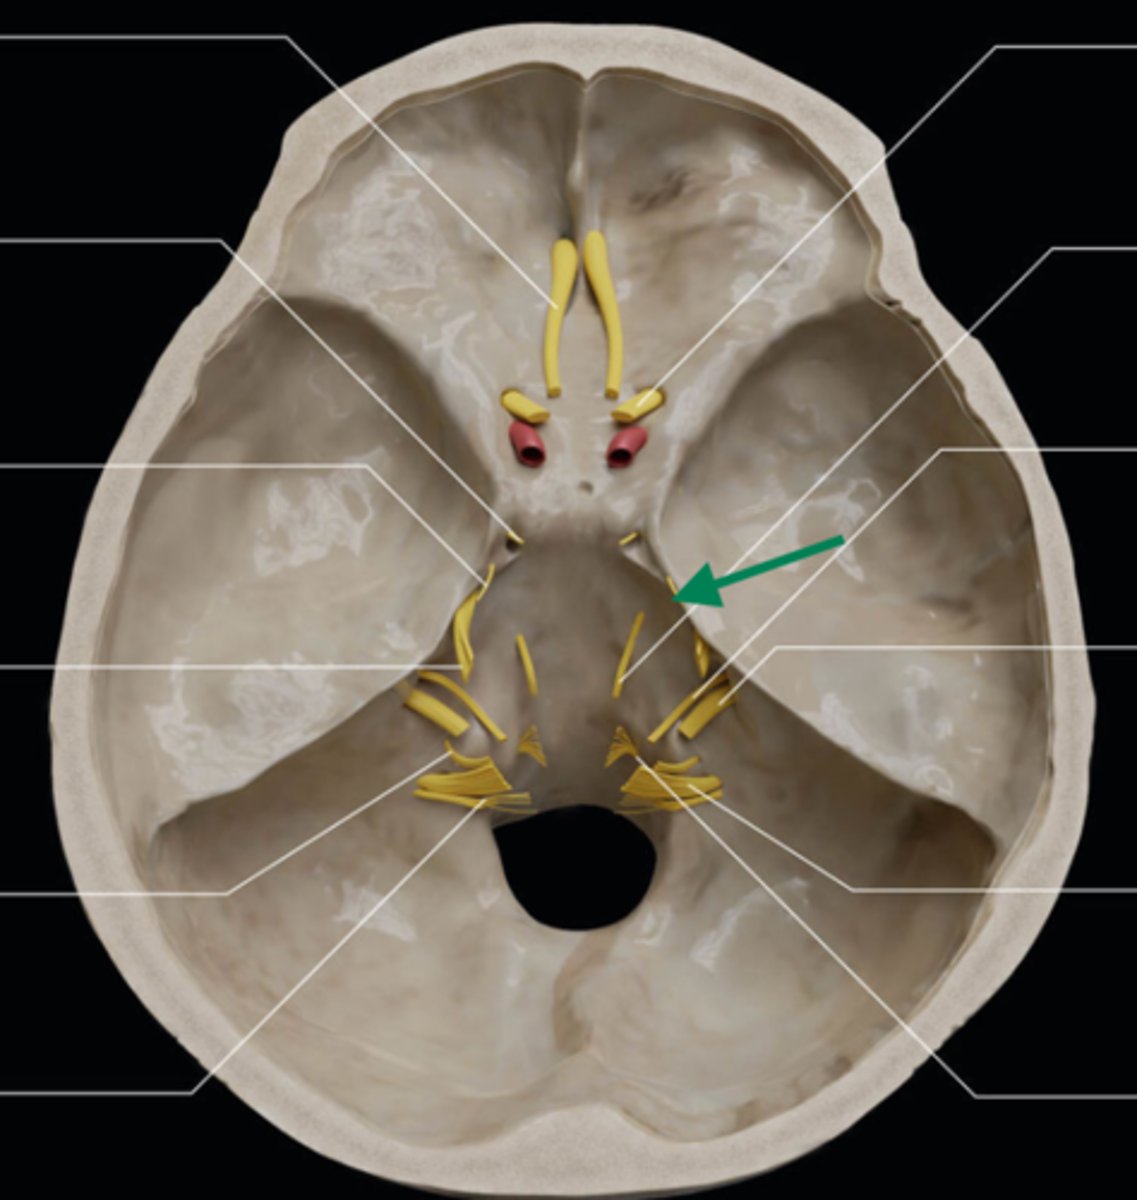

olfactory bulb

olfactory tract

optic nerve (CN II)

internal carotid artery

oculomotor nerve (CN III)

trochlear nerve (CN IV)

abducent nerve (CN VI)

trigeminal nerve (CN V)

facial nerve (CN VII)

vestibulocochlear nerve (CN VIII)

glossopharyngeal nerve (CN IX)

vagus nerve (CN X)

accessory nerve (CN XI)

hypoglossal nerve (CN XII)

optic chiasm

trigeminal ganglion

anterior cranial fossa